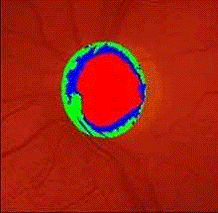

повышением внутриглазного давления. (см. Рис.4) Однако изолированно повышенное

внутриглазное давление не свидетельствует о возникновении глаукомы, если

отсутствуют остальные признаки. На глазном дне у пациентов с глаукомой

наблюдаются изменения зрительного нерва. Определяются экскавация диска

зрительного нерва наряду с истончением нейроретинального пояска, обусловленным

снижением количества нервных волокон и вертикальным перегибом кровеносных

сосудов. (см. Рис.5)

Слой нервных волокон наибольший у краев экскавации диска зрительного

нерва. Уменьшение количества аксонов в этой области приводит к его истончению,

что измеряется отношением площади экскавации к площади диска зрительного нерва.

Анализ этого отношения позволяет идентифицировать расширение экскавации диска

зрительного нерва, встречающееся при глаукоме. (см.Рис.6)